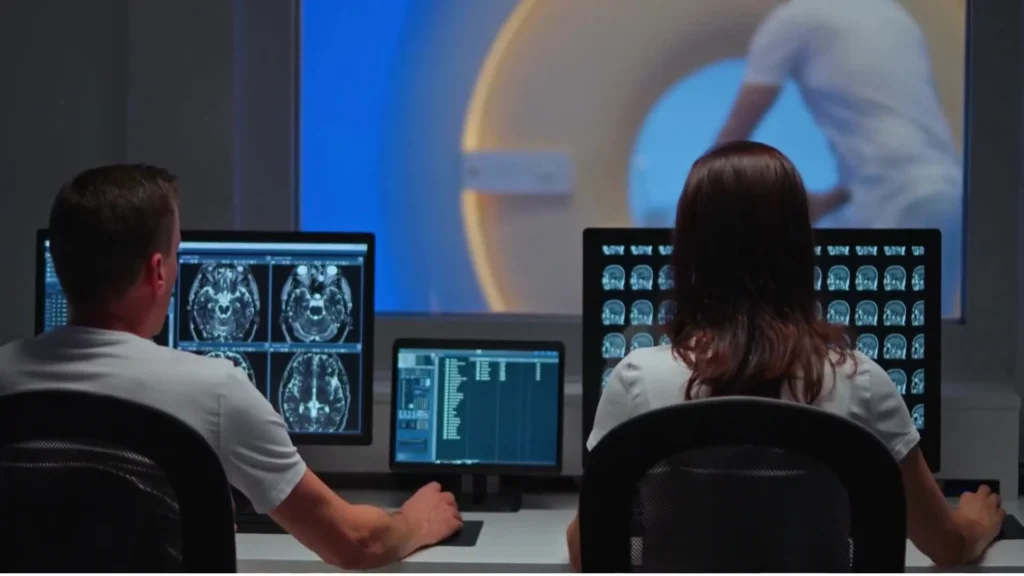

The Marqi Medical members’ journey commences with a comprehensive array of advanced tests, including genomics, blood biomarkers, and detailed imaging to establish the members’ baseline. The exclusive Marqi membership seamlessly integrates cutting-edge technologies with a dedicated medical team, including longevity physicians working harmoniously with primary care physicians and concierge doctors.

Members gain unprecedented access to comprehensive, cutting-edge health assessments that go far beyond traditional check-ups.

Early Detection Saves Lives

> Imaging